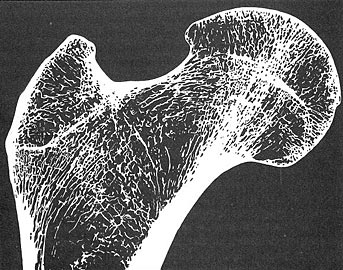

Imaging of bone forms used in biomimicry: Professor A Robinson |

Drawing of bone forms used in biomimicry: Professor A Robinson |